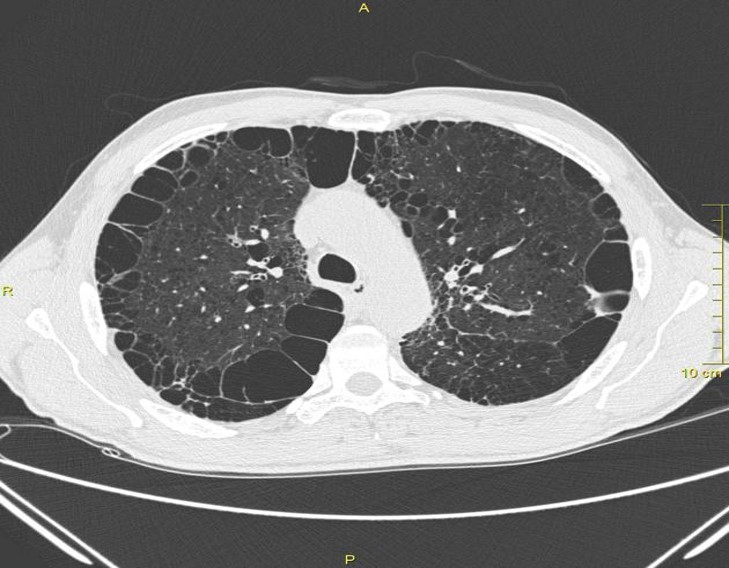

Lung Bullae/Bleb

Blebs (pockets of air) in COPD pt